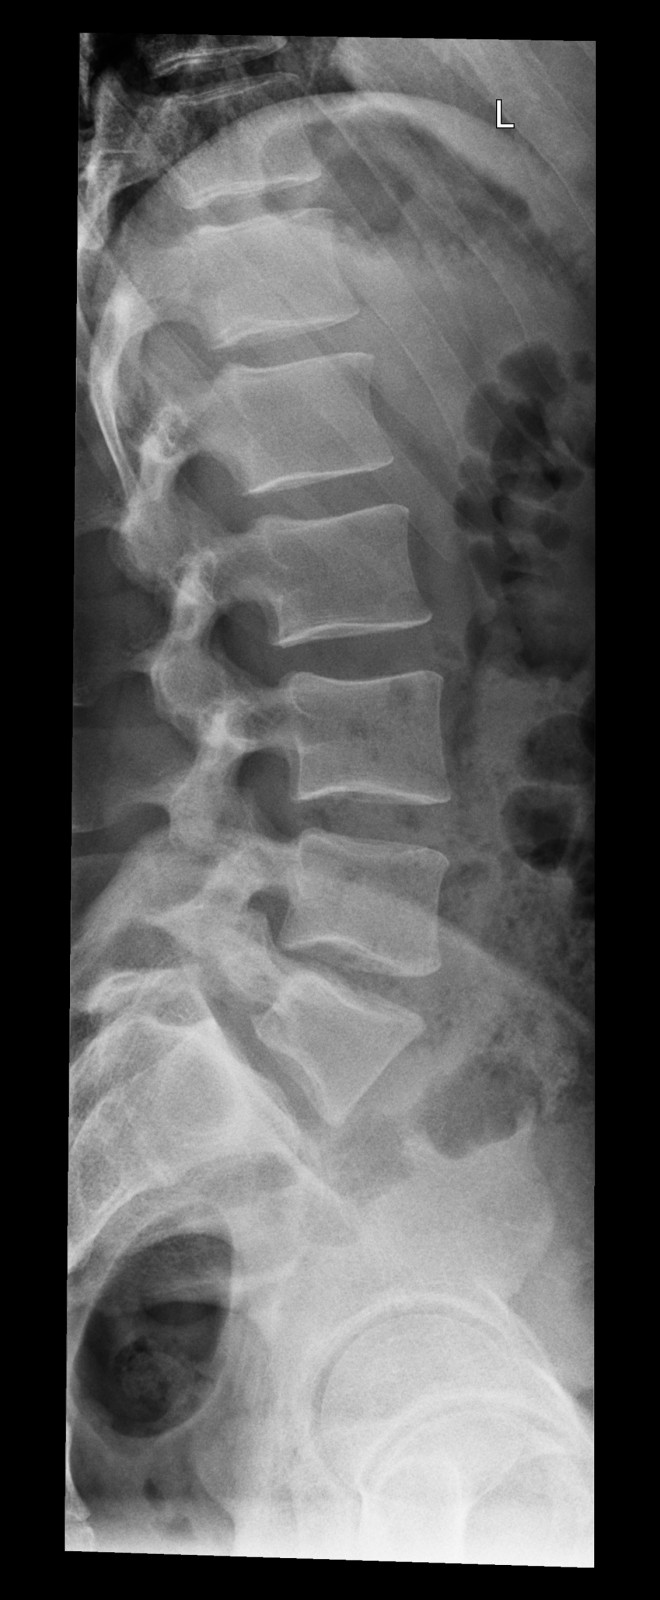

Röntgenfall des Monats Juni 2017 mit Auflösung

34 jähriger Patient mit exazerbierter Lumbago. Beruf: Plattenleger

seitlich

Bild vergrössern

Link zur Auflösung mit ausführlichem Befund:

https://www.radiologie24.ch/radiologie-mediathek/roentgenfall_des_monats